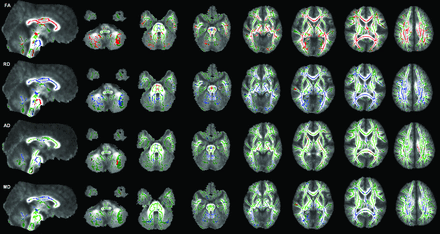

The WM structures with significant change and their mean quantitative values are summarized in On-line Table 4. The TPF in patients with ARSACS had higher FA, lower RD, higher AD (P < .05), and a comparable mean diffusivity (P > .05) compared with control participants. In the patients, CST in the brain stem revealed significantly lower FA, increased RD, increased mean diffusivity (P < .05), and no remarkable change in AD (P > .05). TBSS maps showed consistent results with these measurements of ROIs outlined from color FA maps (Fig 3).

TBSS (family-wise error–corrected threshold-cluster extend voxel p maps) display clusters with significantly different FA, RD, AD, and mean diffusivity compared with sex- and age-matched control participants at P < .05. For all diffusion measures, blue shows increased values and red shows decreased values. FA skeleton projected on a mean FA map is shown in green.

TBSS revealed extensive reductions in FA, accompanied by increased RD in the supratentorial WM, including the entire corpus callosum, both cingula, fornices, superior and inferior longitudinal fasciculi, the inferior fronto-occipital fasciculi, corona radiata, internal capsules, and thalami. Bilateral superior cerebellar WM and vermis and CST in the medulla oblongata and midbrain showed a similar pattern of FA and RD changes. The extent of increased mean diffusivity and AD followed that of FA and RD changes in decreasing order. However, reduced AD was present along the internal capsules and midbrain, medulla oblongata, the splenium of the corpus callosum, and bilateral frontoparietal WM. No remarkable decrease in mean diffusivity was present except for a few small clusters in the subcortical temporal WM (Fig 3).